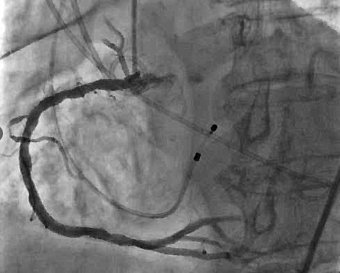

冠脉造影及介入治疗:将ACIST CVi血管造影注射系统调整至冠脉造影模式,完善冠脉造影。结果示:LM未见明显狭窄,LAD近端80%狭窄,严重钙化,IVUS可见360°钙化。回旋支少量斑块浸润,右冠状动脉30-40%狭窄。决定处理LAD,由于患者存在严重钙化,使用Shockwave球囊预处理打开钙化,后植入3.0*24mm +3.5*24mm药物涂层支架,效果满意。

支架植入后